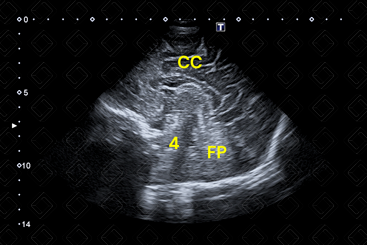

As imagens rotineiramente são obtidas nos planos coronal e sagital. As imagens coronais são obtidas colocando-se o transdutor transversamente pela fontanela anterior e angulando o feixe de ultrassom da frente para trás. As imagens sagitais são obtidas posicionando-se o transdutor em orientação longitudinal na fontanela anterior e angulando o feixe do meio para lateral (figuras 1 a 6).

Descrição da figura 3: Ultrassonografia transfontanela, plano sagital na linha média. CC – corpo caloso; FP – fossa posterior; [cms-watermark] 4 – ventrículo.